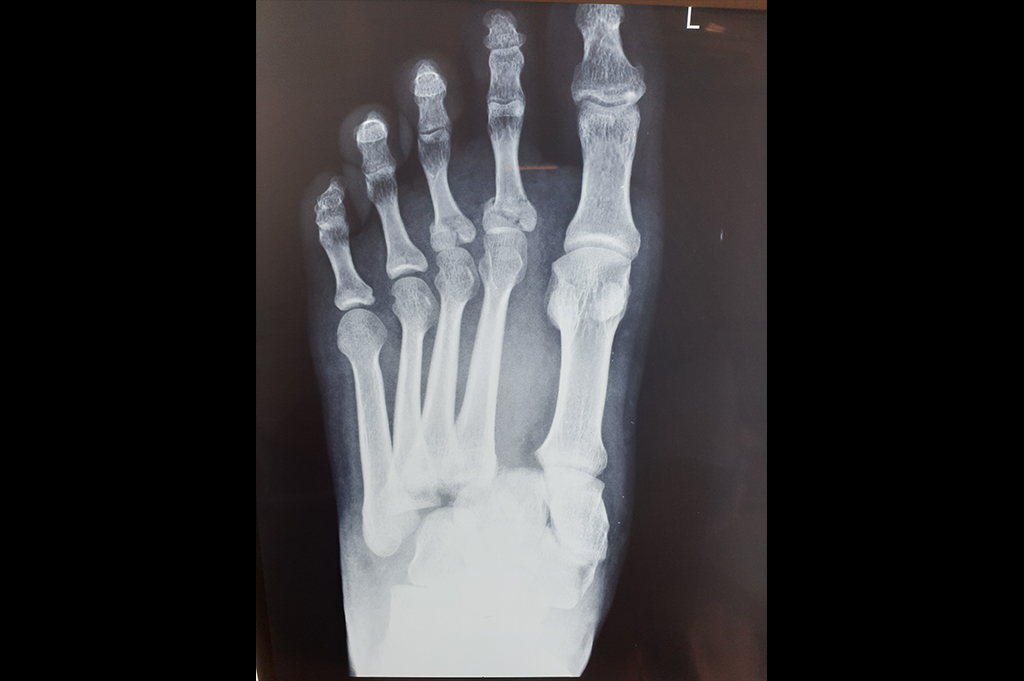

Metarsals with dislocations Lisfranc